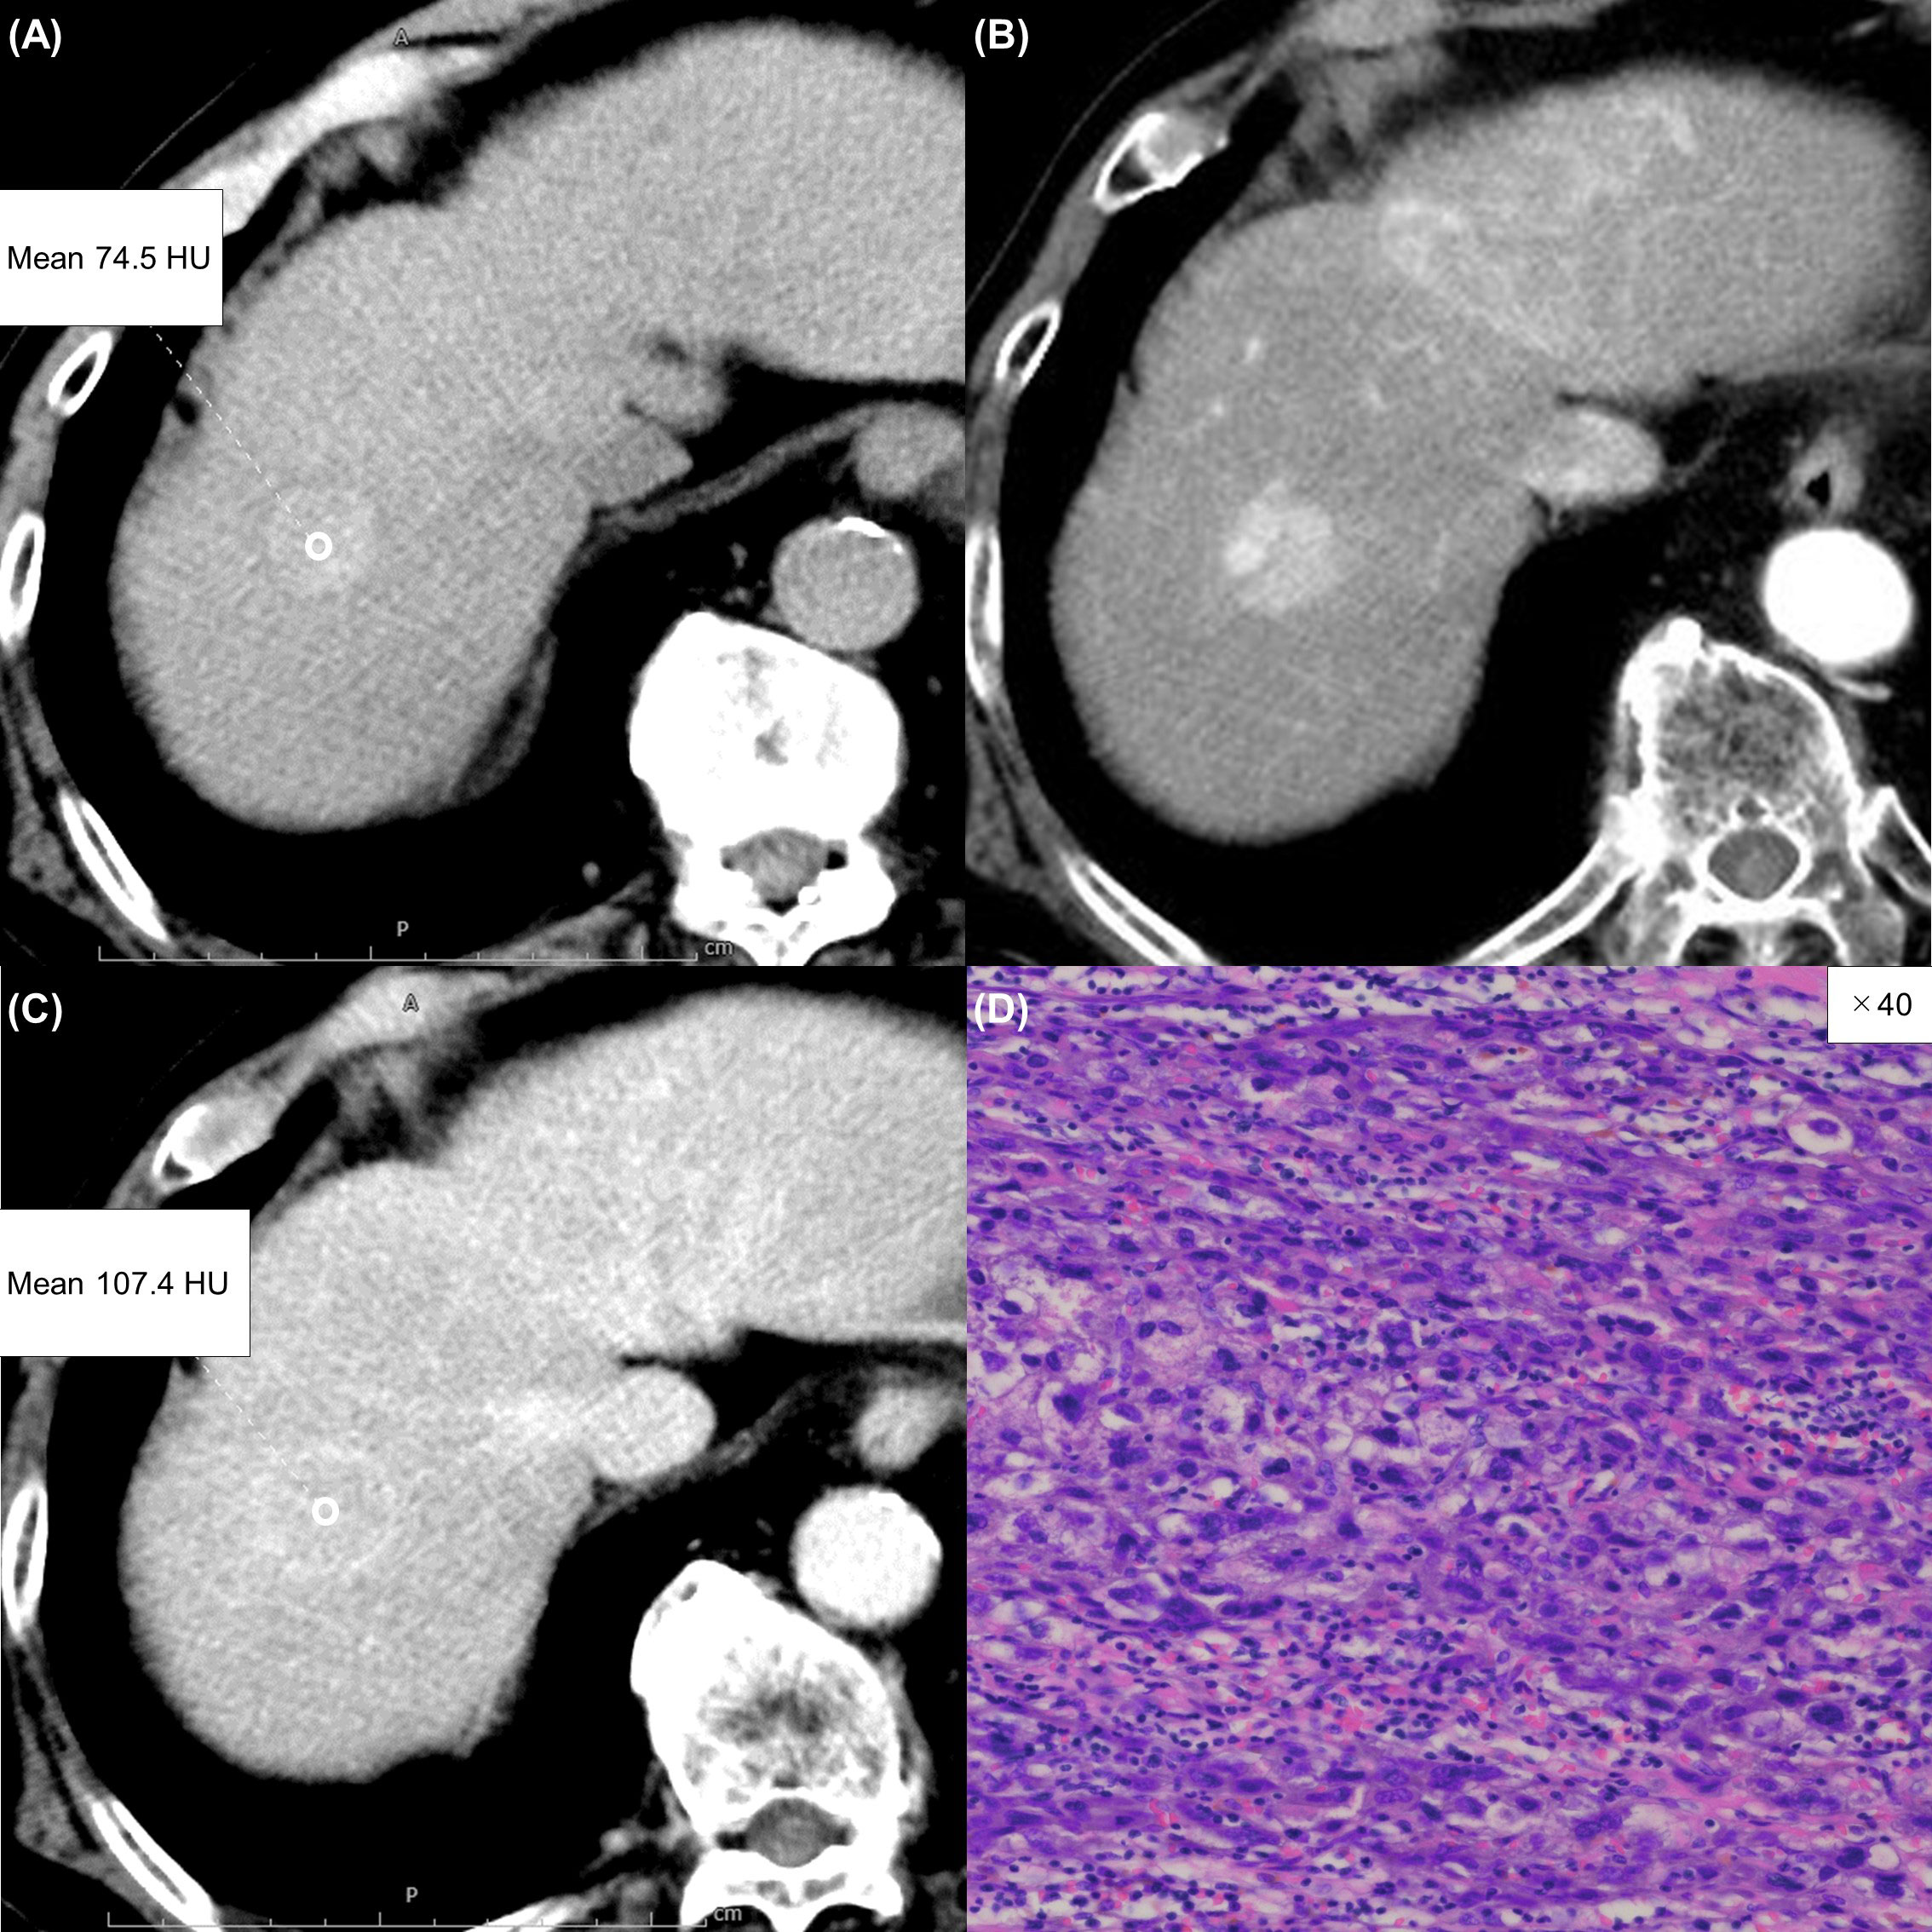

Figure 5 An 85-year-old man with an atypical hepatocellular carcinoma. Precontrast CT shows a round hyperdense lesion in the right lobe of the liver (A). The lesion shows homogeneous enhancement during the arterial phase (B) and slight washout during the equilibrium phase (C). Because of differences in the judgment of washout between readers 1 and 2, reader 3 made the final judgment. Tumor extracellular volume fraction (fECV) is 20.3%, which is below the cutoff value (41.5%). No fibrosis is observed in the tumor histopathologically (D, ×40, hematoxylin-eosin stain).

Figure 6 A 57-year-old man with an atypical intrahepatic cholangiocarcinoma. Precontrast CT shows a hypodense lesion in the right lobe of the liver (A). The lesion shows inhomogeneous enhancement during the arterial phase (B) and slight washout during the equilibrium phase (C). These imaging findings can lead to a misdiagnosis of hepatocellular carcinoma. A round region of interest was placed in the solid part of the tumor that showed the most remarkable enhancement. Tumor extracellular volume fraction (fECV) is 49.1%, which exceeds the cutoff value (41.5%). Fibrosis is observed in the tumor histopathologically (D, ×100, hematoxylin-eosin stain).